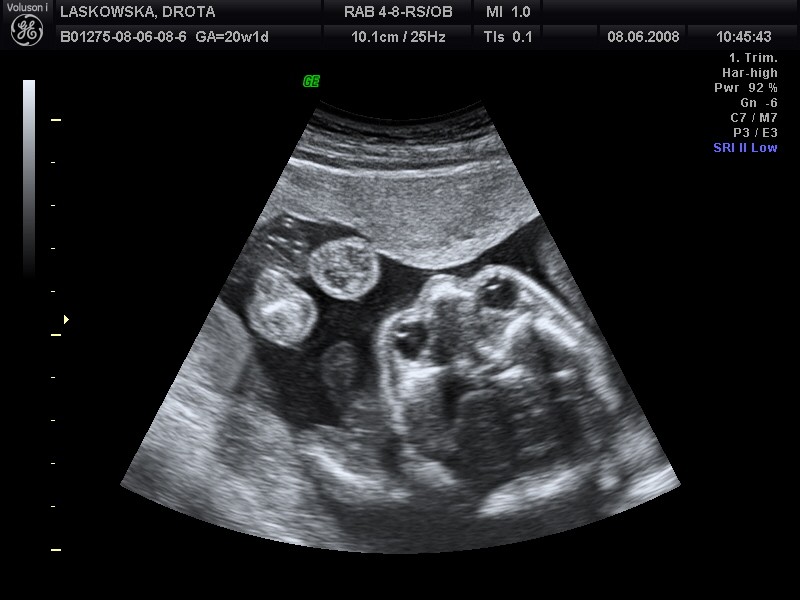

A tu pozwoliłam soebie wkleić Twoje fotki tzn Oliwii:-p

Piękne foty:tak:

Załączniki

• laskowska3yd6.jpg

laskowska3yd6.jpg

74,7 KB · Wyświetleń: 52